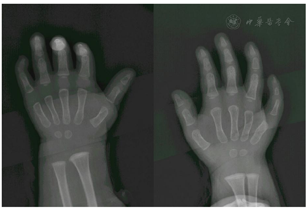

患儿双侧小指掌侧和背侧外观见图1。小指情况见图2。患者双手X线正位片,可见小指发育不良,中远节明显,近指间关节间隙仍可见(图3)。

结合患者的双侧小指畸形查体表现,其细蜡烛样外形,掌侧皮肤形同背侧,屈曲功能的障碍及一侧小指掌侧指甲畸形的特点,可以明确诊断这是一例典型的先天性掌侧甲综合征。

本例报道主要依赖外观和查体表现,虽然仅有右侧小指有远端掌侧指甲,覆盖约2/3以上的掌侧末端,但凭双侧小指的尖细外观,掌侧皮肤无屈曲横纹同背侧皮肤,指间关节无主动活动等查体表现,基本可以明确诊断。仔细观察,可以发现右侧环小指的指蹼较正常位置略深,也与前人总结的经验相符。双侧小指掌指关节侧方均有小皮丘赘生物,可以怀疑这类畸形与尺侧不全发育的多指的可能的相关性。因病例较少,以后如有可能需要进一步的基因学检测来明确。